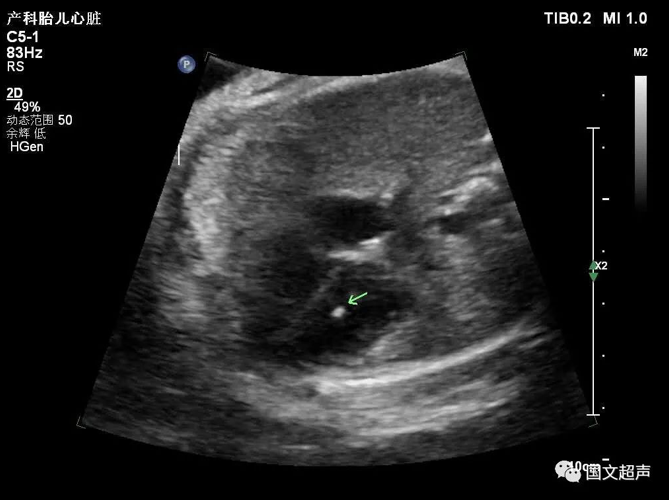

三.關(guān)于心室強(qiáng)回聲光點(diǎn)

胎兒心室內(nèi)強(qiáng)回聲光點(diǎn)不是一種心臟畸形,它只是一個聲像圖表現(xiàn),是胎兒染色體異常的一種潛在體現(xiàn),也被稱為超聲軟指標(biāo)(不是器質(zhì)的異常,其他的軟指標(biāo)還有NT增寬、腎盂分離、側(cè)腦室增寬、腸管回聲增強(qiáng)、四肢長骨短、鼻骨短小等等)。

大部分強(qiáng)回聲光點(diǎn)隨孕周增加而縮小,回聲強(qiáng)度也逐漸減弱。到足月妊娠幾乎完全消失,少數(shù)則可一直存在,直至分娩,甚至產(chǎn)后超聲仍能觀察到。